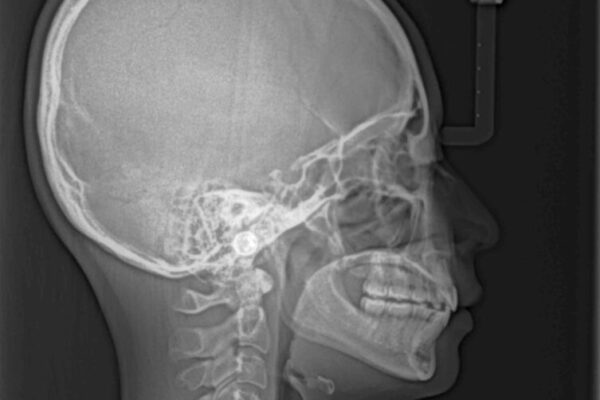

上下前歯が著しく前突している状態であったので、上下左右の第1小臼歯4本を抜歯し、ワイヤー装置にて矯正治療を行うこととしました。

舌の突出癖により、前突になったと考えられたため、舌のトレーニングをしっかりと行うよう指導しました。

上下の前歯が突出しており、口が閉じにくいとのことで来院された患者様です。